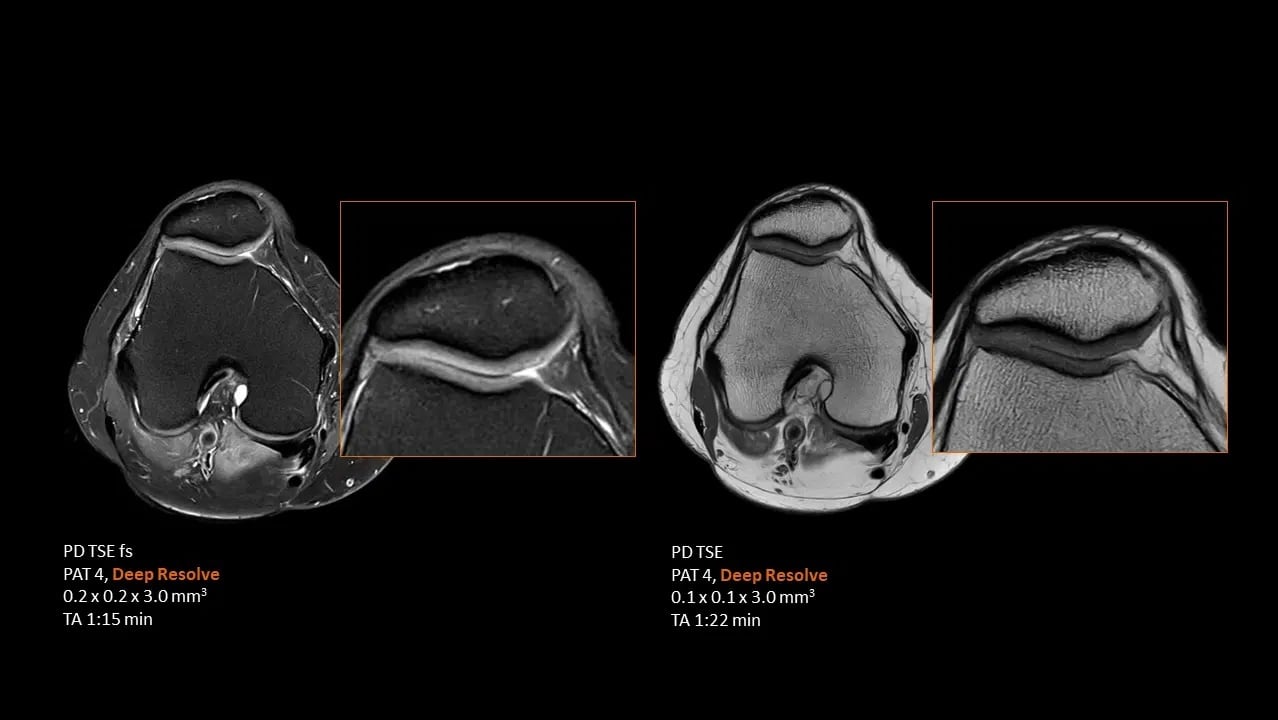

MSK

High resolution orthopedic imaging at 1.5T with Deep Resolve

Study-ID:1aaaa5194. Acquired on MAGNETOM Flow. Platform with 70cm.

Unrivaled speed with Deep Resolve

Deep Resolve, an AI powered tool used to boost signal and resolution, enables you to exploit advanced acceleration techniques while maintaining extraordinary clarity. Faster scans, faster results, better patient experience!